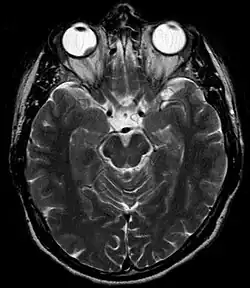

Tomografia komputerowa i rezonans magnetyczny

Tomografia komputerowa (TK) i rezonans magnetyczny (MRI) mogą być przydatne do oceny rozprzestrzeniania się pozagałkowego guza[26].